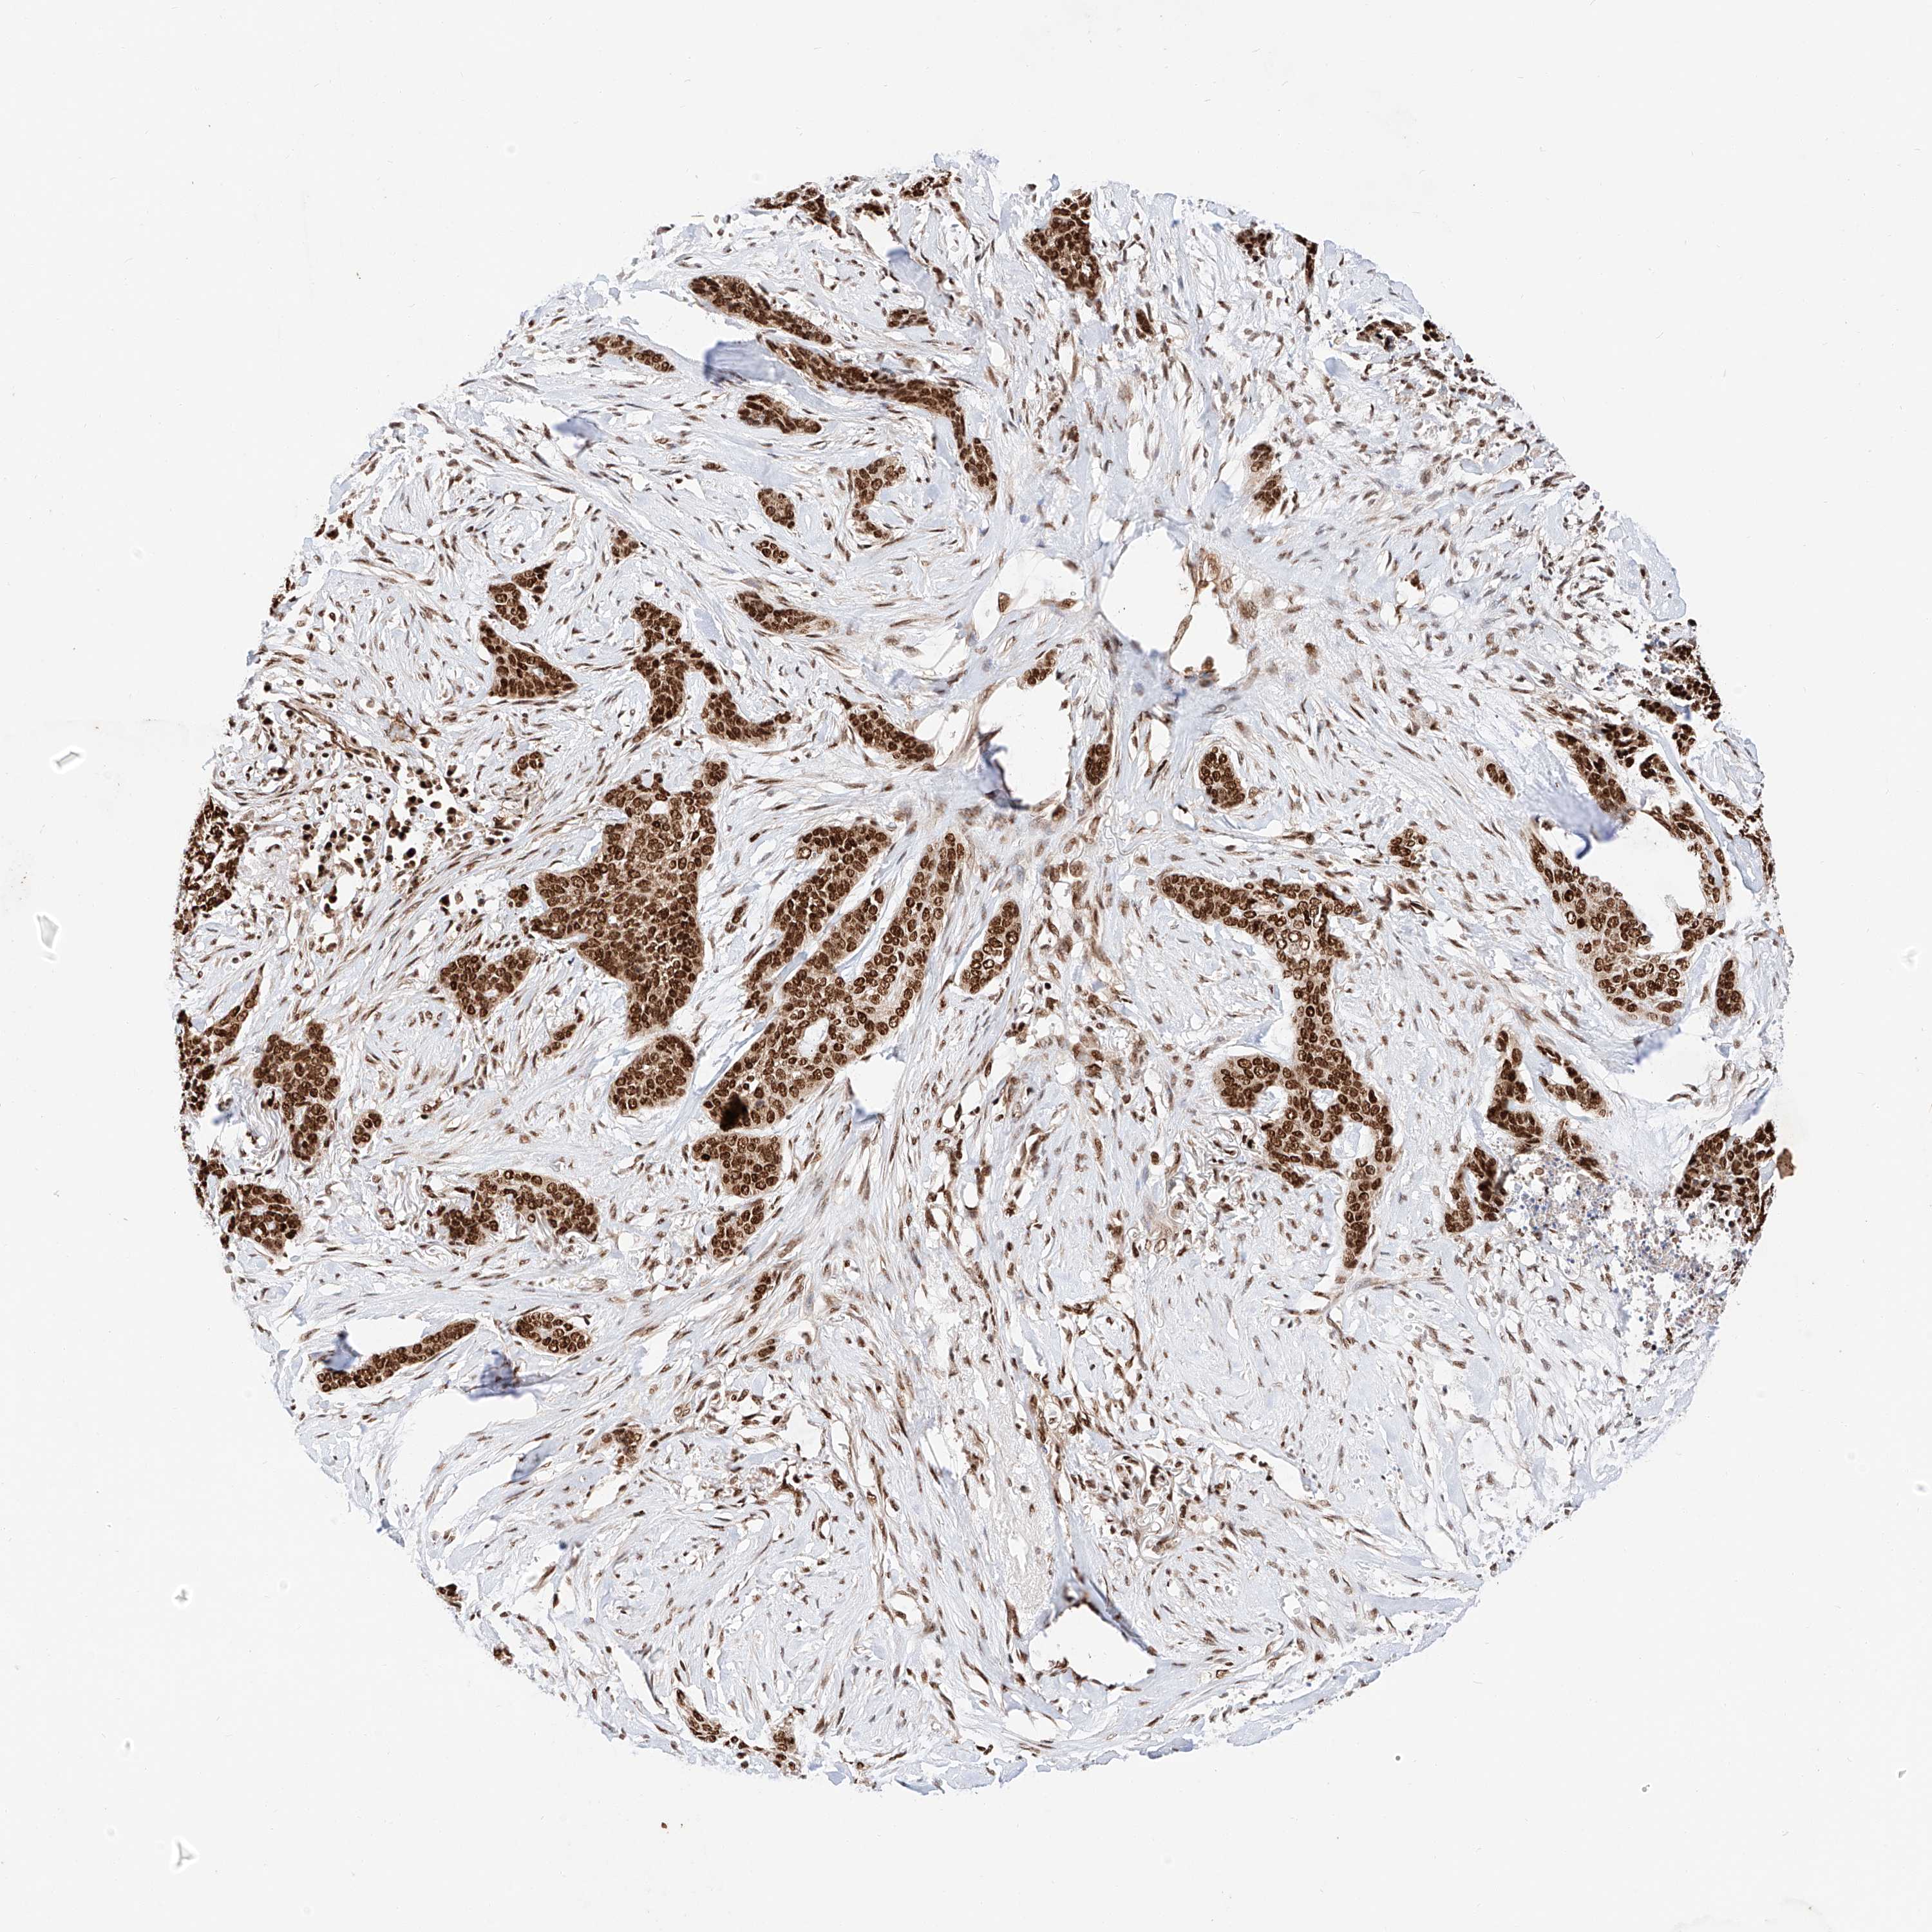

SKIN CANCER - Protein expressioni

A mouse-over function shows sample information and annotation data. Click on an image to view it in a full screen mode. Samples can be filtered based on level of antibody staining by selecting one or several of the following categories: high, medium, low and not detected. The assay and annotation is described here.

Antibody stainingi

Antibody staining in the annotated cell types in the current human tissue is reported as not detected, low, medium, or high, based on conventional immunohistochemistry profiling in selected tissues. This score is based on the combination of the staining intensity and fraction of stained cells.

Each image is clickable and will lead to virtual microscopy that enables deeper exploration of all samples and also displays staining intensity scores, fraction scores and subcellular localization as well as patient and tissue information for each sample.

Antibody HPA028926

Staining

Medium

Intensity

Weak

Quantity

<25%

Location

Nuclear

Squamous cell carcinoma, NOS